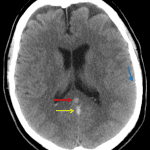

- Hyperdensity in the left transverse sinus, straight sinus, vein of Galen, and in veins coursing along the left cerebellar hemisphere

- Scattered linear hyperdensities within sulci in the bilateral cerebral and cerebellar hemispheres

- Small acute parenchymal hemorrhage in the high right frontal lobe

- Hypodensity in the left temporo-occipital region

- Right frontal sinusitis

- Venous sinus thrombosis with associated hemorrhage and parenchymal edema

Hyperdensity in the left transverse sinus, straight sinus, vein of Galen, and in a vein coursing along the left cerebellar hemisphere concerning for venous thrombosis. Small acute parenchymal hemorrhage in the high right frontal lobe raises concern for superior sagittal sinus and/or cortical vein thrombosis as well. Recommend brain MRI with and without contrast for further evaluation.

Scattered linear hyperdensities within sulci in the bilateral cerebral and cerebellar hemispheres, which may represent small volume subarachnoid hemorrhage and/or additional small thrombosed veins. No hydrocephalus.

Hypodensity in the left temporo-occipital region consistent with edema/developing venous infarct.

Right frontal sinusitis.